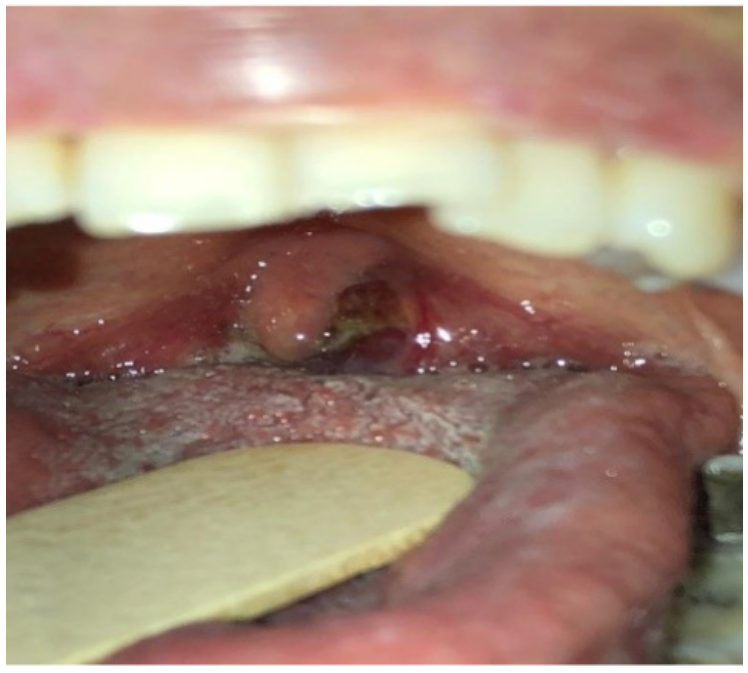

En junio del 2018 presentó aumento de tamaño y dolor en amígdala izquierda asociado a cambios en diámetro y textura (figura 1), asociado a pérdida de peso no voluntario, odinofagia y adenopatías cervicales bilaterales mayores a 1 cm de diámetro, de consistencia firme y no dolorosas; por dichos hallazgos se sospechó de enfermedad linfoproliferativa postrasplante, carcinoma escamocelular o enfermedad por citomegalovirus. Se realizaron estudios complementarios, carga viral para CMV negativa, tomografía de cuello con hallazgos de adenomegalias cervicales bilaterales (figura 2), tomografía de tórax sin lesiones evolutivas en parénquima pulmonar, ni otras alteraciones (figura 3).

Figura 1 Crecimiento amigdalino con cambios en coloración